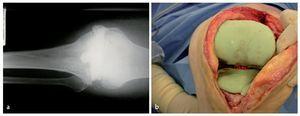

Fig. 8 Desde el punto de vista facultativo, ahora se puede conformar un espaciador monobloc (a) o un espaciador articulado para el macizo condíleo y el platillo tibial (b) formado por cemento de polimetilmetacrilato, que rellena el espacio hueco del surco articular ensanchado y que cierra a ras las superficies óseas que suelen sangrar fuertemente. El cemento debe contener gentamicina y clindamicina, que se complementan sinérgicamente cuando son liberadas. En caso de ser necesario según antibiograma, se puede añadir vancomicina y colistina. a) Radiografía de un espaciador monobloc in situ. b) Espaciador articulado «hecho a medida» in situ.